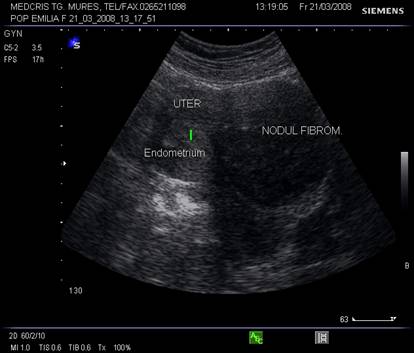

Fig, nr.380. Nodul fibromatos intramural si subseros al peretelui anterior uterin, in sectiunea sagitala a ecografiei abdominale